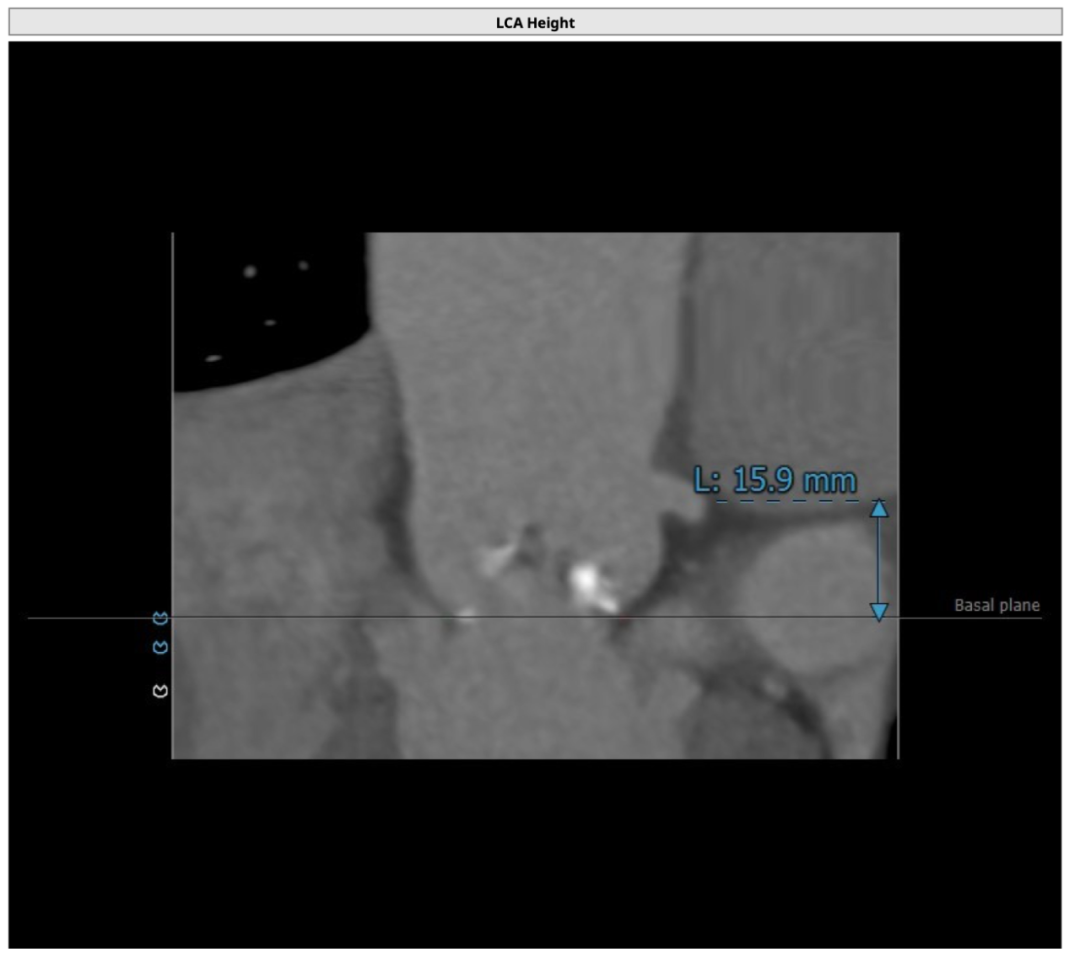

该名患者为Type 0型二叶瓣,钙化分布不对称,瓣叶有轻度增厚。瓣环最短径为19.6mm,最长径为25.2mm,平均瓣环直径为22.4mm。左冠开口高度15.6mm,右冠开口高度15.9mm。

左冠开口

右冠开口